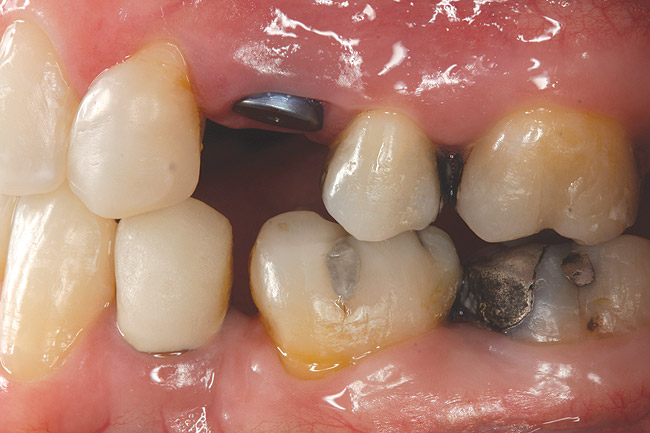

Fig 11. Corticotomy SFOT. A 42-year-old male presented with a history of extraction orthodontic therapy.

Fig 12 (and Fig 13). Incisors were too upright and had severe incisal wear. He was concerned about esthetics of the worn teeth and his insufficient lip support. Progress photo and panorex 9 months after corticotomies were performed on Nos. 6 through 11. Previous extraction sites were reopened orthodontically to improve function and fill lip support. Incisal edges were restored provisionally with composite resin. Note that despite the creation of adequate spaces to replace missing teeth, there is inadequate room for placement of dental implants because of severe tipping of all the anterior teeth. Osteotomy SFOT may have been a better choice because it would have allowed needed alveoloskeletal correction (without excessive tipping) instead of the primarily dentoalveolar correction common in corticotomy SFOT. Restorative dentist: Brad Jones, DDS.

Fig 13 (and Fig 12). Incisors were too upright and had severe incisal wear. He was concerned about esthetics of the worn teeth and his insufficient lip support. Progress photo and panorex 9 months after corticotomies were performed on Nos. 6 through 11.